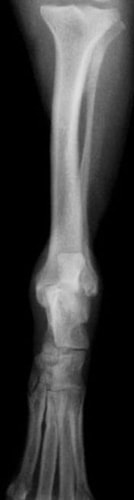

後肢の骨折:大腿骨骨折

![]() 骨折時 |

![]() 手術後 |

![]() 骨折治癒 |